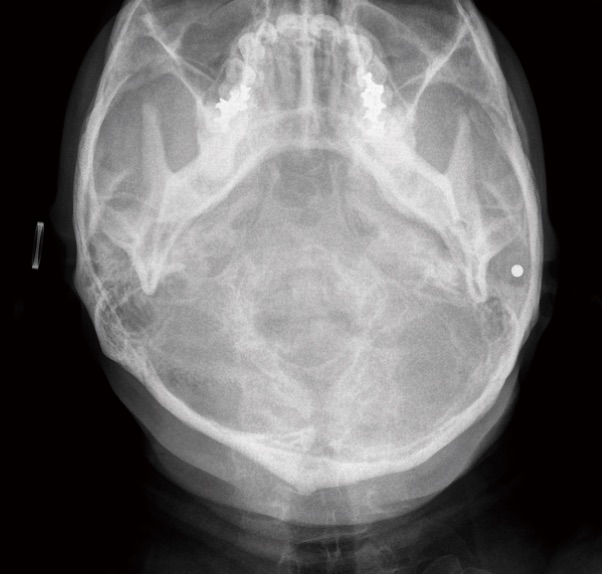

頭部一軸方向撮影